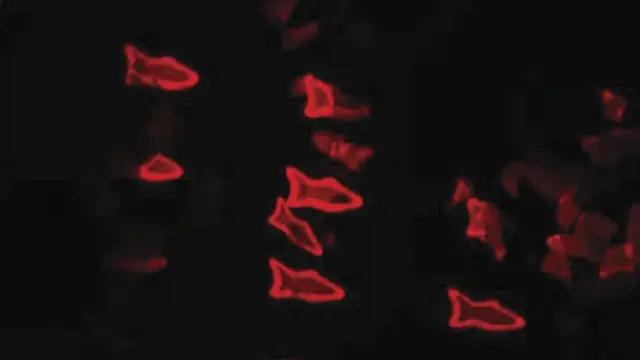

Ingenieros de la Universidad de California han creado microbots con forma de pez impresos en 3D que podrían administrar medicamentos en el interior del cuerpo.

Estos microbots tienen un grosor más pequeño que el de un cabello humano y forma de pez, y han sido fabricados con una impresora 3D aplicando una tecnología de impresión óptica de alta resolución.

A diferencia de otros robots microscópicos creados hasta el momento, para este estudio se realizó un diseño más complejo con la finalidad de que el dispositivo pueda ofrecer más funciones. "Con nuestra tecnología de impresión 3D no estamos limitados a la forma de pez. Podemos construir otros modelos inspirados en otros organismos biológicos, como las aves", asegura Wei Zhu, uno de los autores de la investigación.